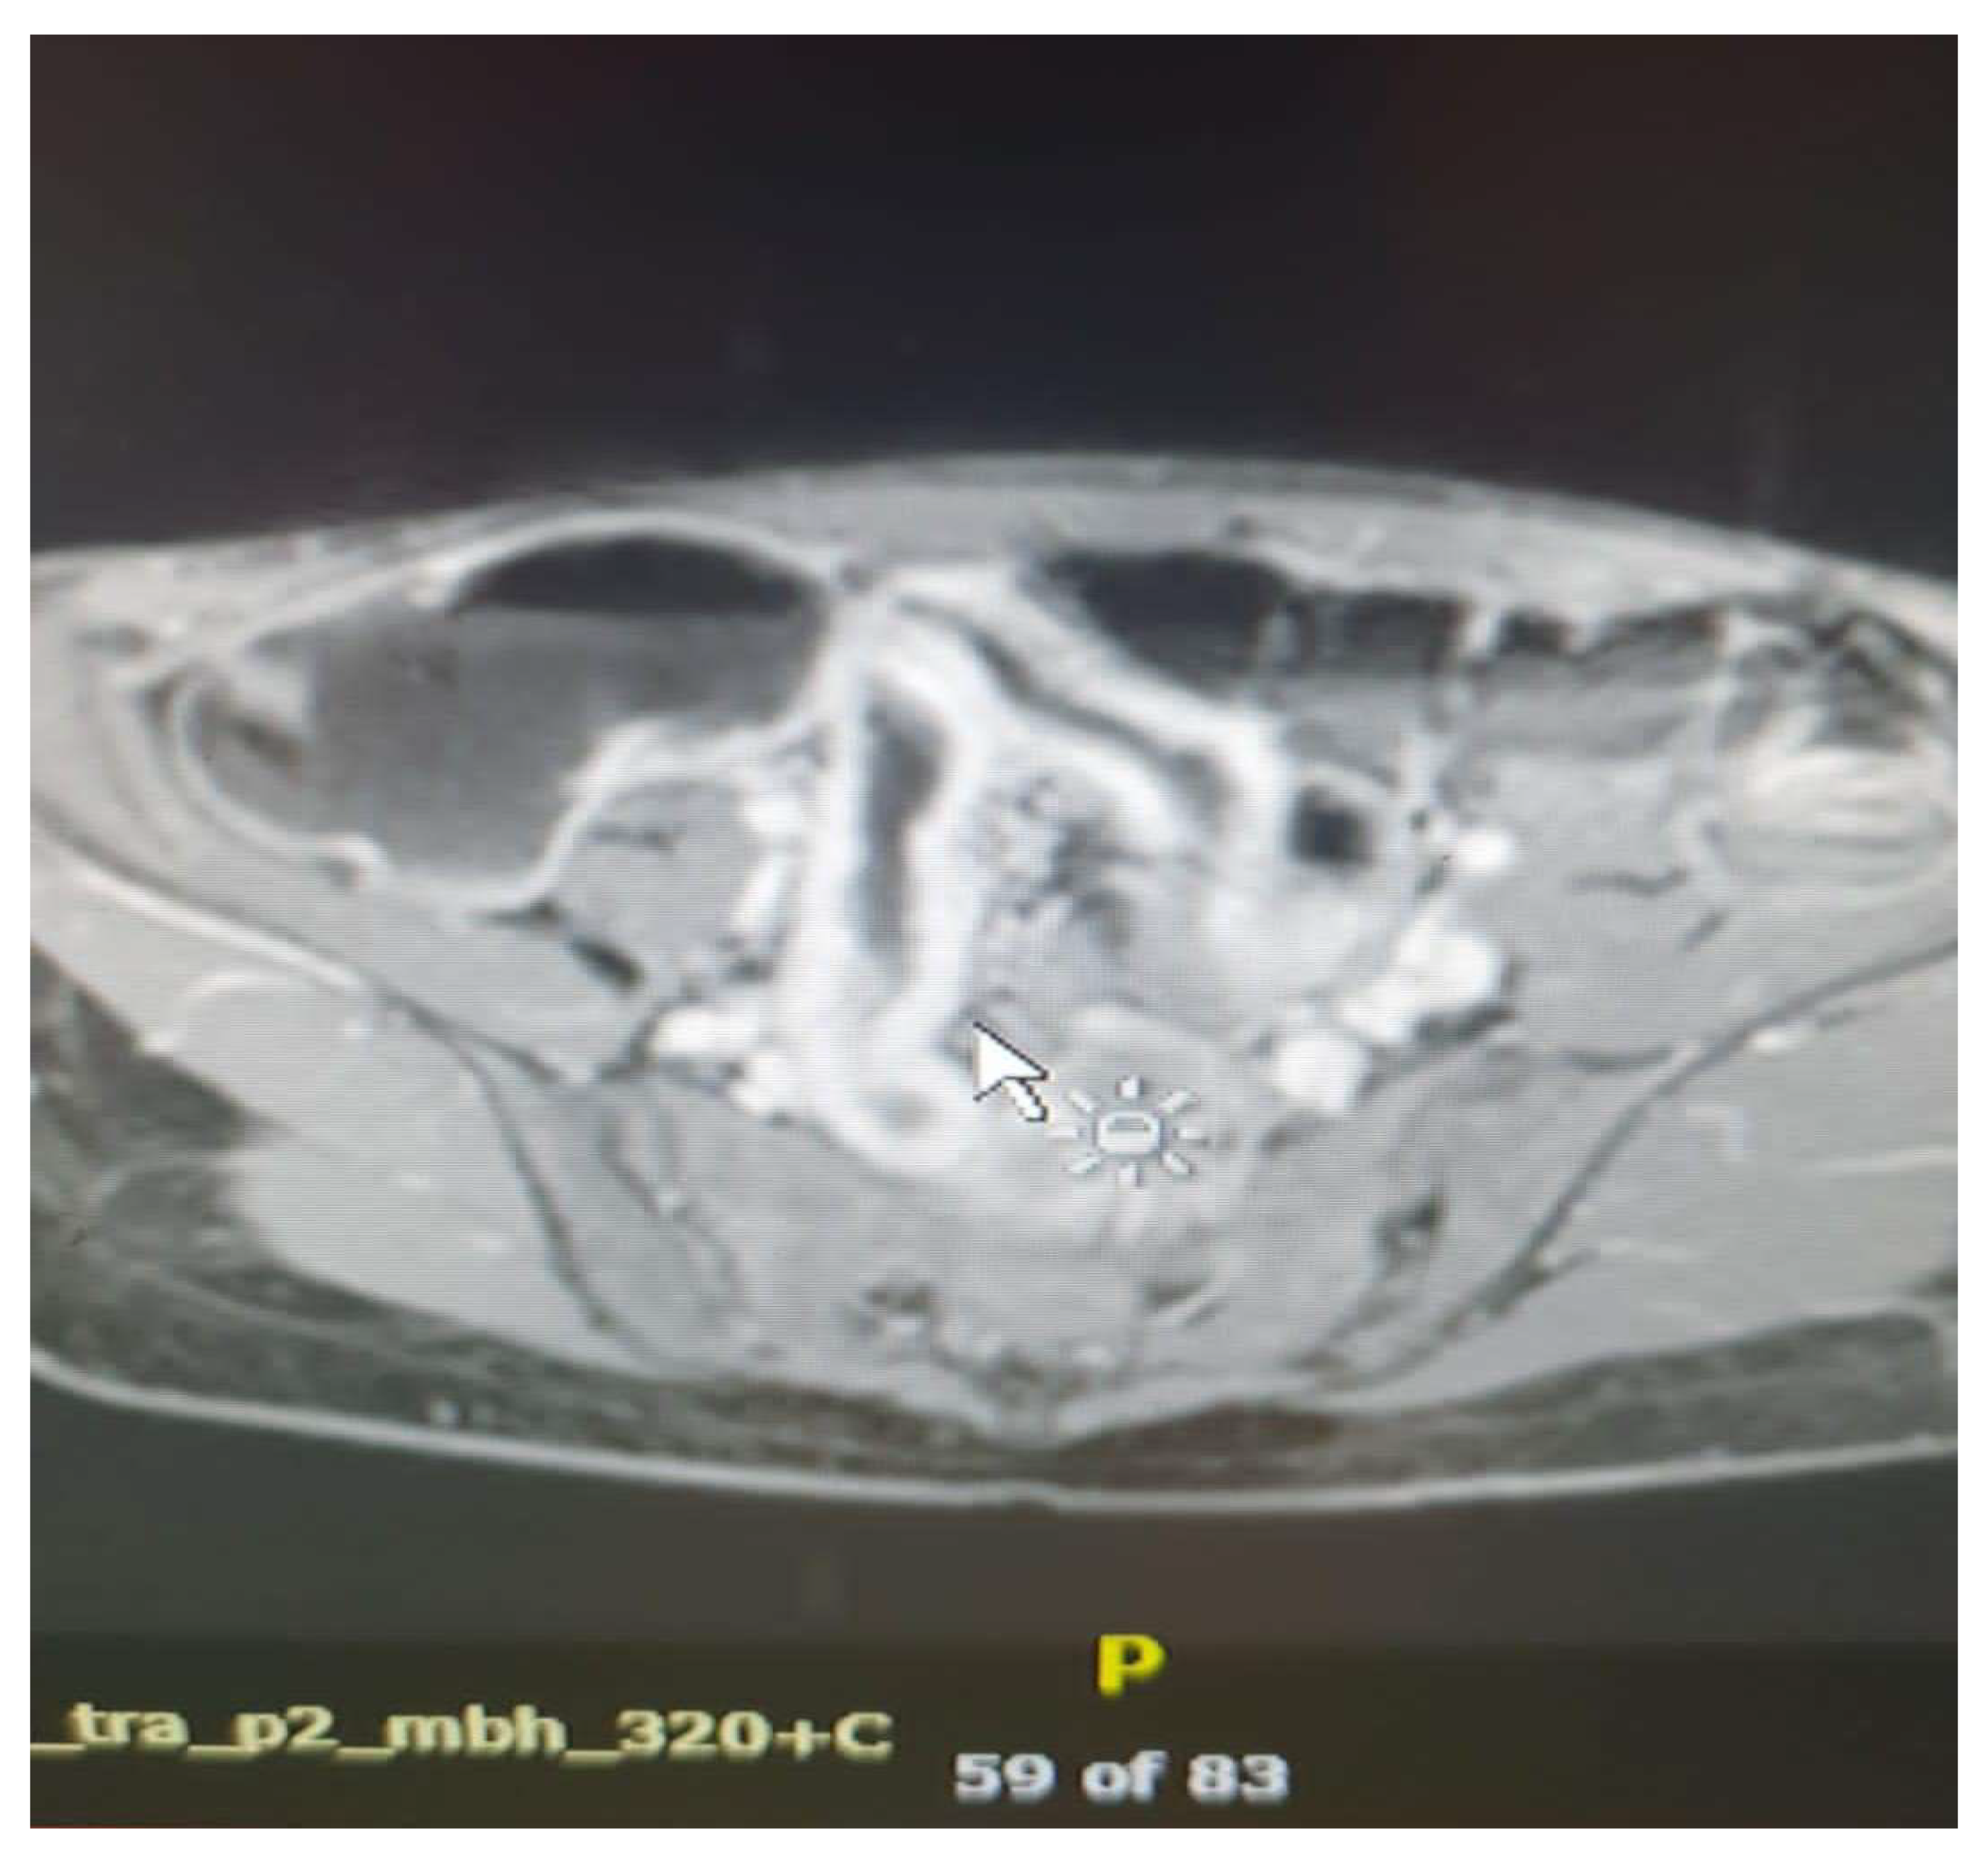

- Ulceration

- Focal defects, fine disruptions of the mucosal contour - small signs of T2 hyposignal or intense post-contrast enhancement[50]

- Requires adequate distension of the small bowel (Figure 4 ).

- Fistulas

- They may be enteroenteric, enterocolic, enterovesical, or perianal [8]

- Fistulae occur following advanced penetrating disease [8]

- Abcesses

- Abscesses are found in the abdominal cavity, intestinal wall, or perianal area[8]